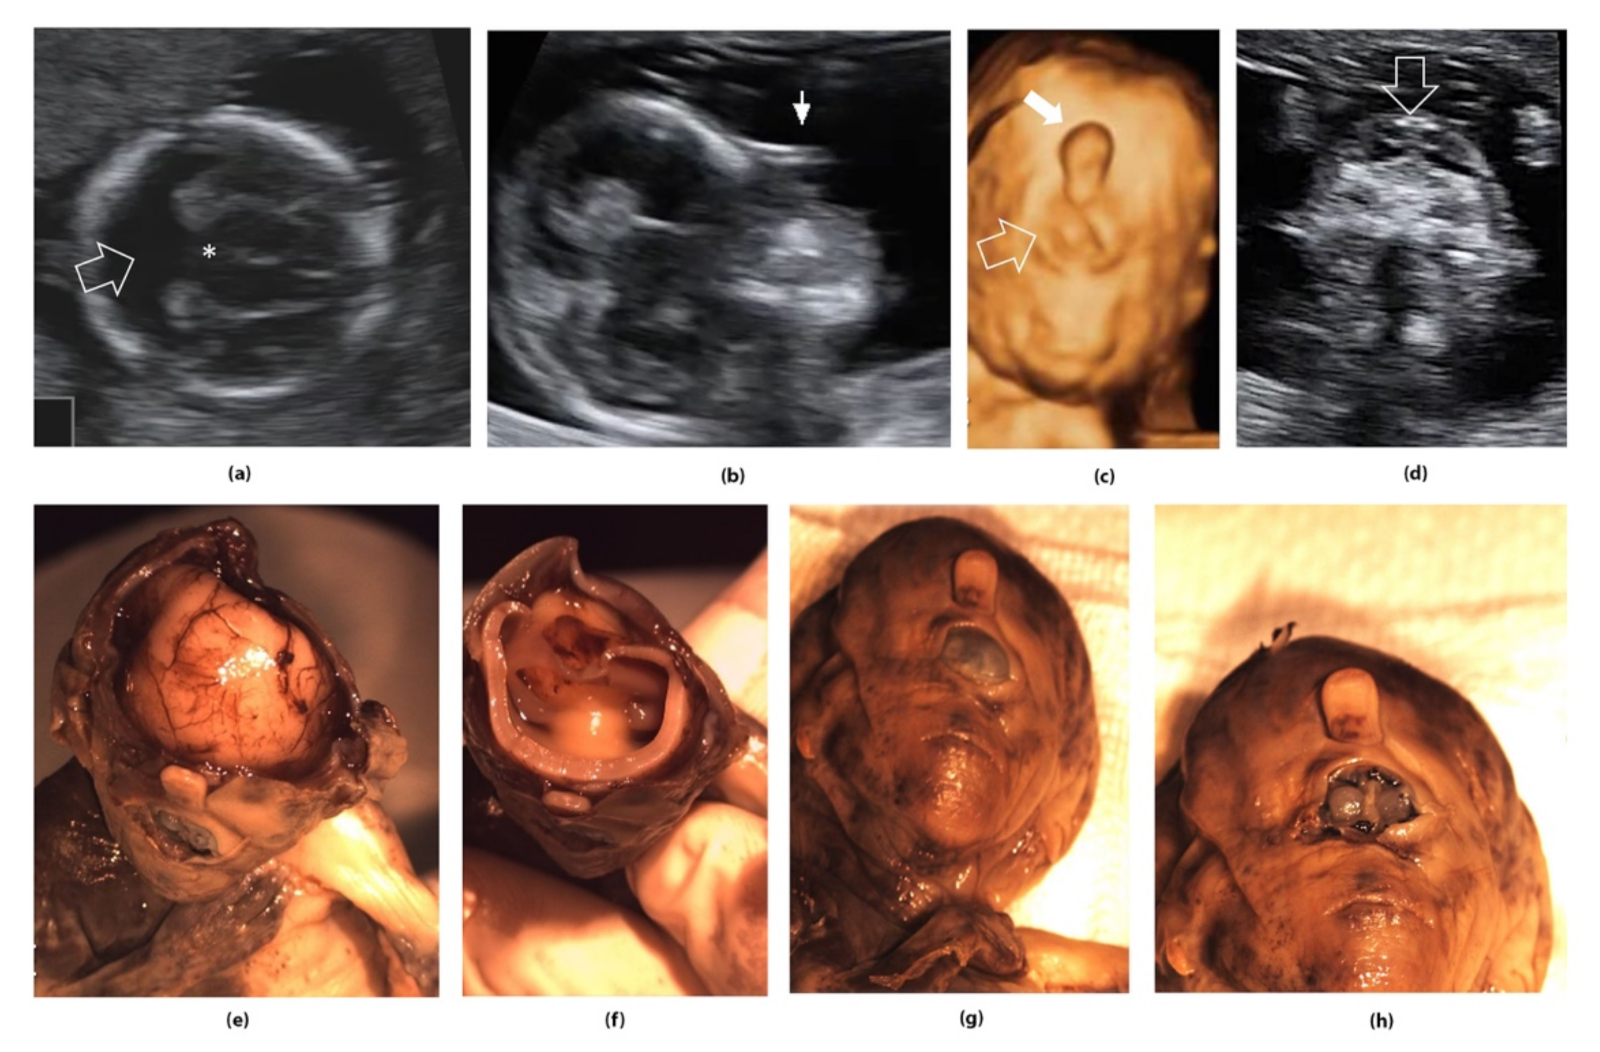

Figure 3.

Alobar holoprosencephaly detected in the first trimester of pregnancy (12 weeks of gestation). (a) Absence of the falx cerebri and fusion of the lateral ventricles (arrow) and thalami (star); (b) Proboscis, 2D evaluation; (c) 3D evaluation of the fetal face, showing proboscis (arrow) and cyclopia (open arrow); (d) extreme hypotelorism—synophtalmia (arrow); (e–h) pathology demonstration of the ultrasound findings: complete failure of the brain to divide into right and left hemispheres; (e) with the loss of midline structures of the brain and fusion of the cavities of the brain; (f) proboscis and very closely spaced eyes (synophtalmia/ethmocephaly).

Most CNS anomalies are identified using 2/3D neurosonography performed by an experienced examiner (83.7% of CNS malformations were identified in this way), while fetal MRI is used only in limited cases [21,22,23]. However, although there are controversial reports on the management of CNS anomalies, some studies show that fetal MRI increases the accuracy of detecting CNS anomalies [24,25,26,27].